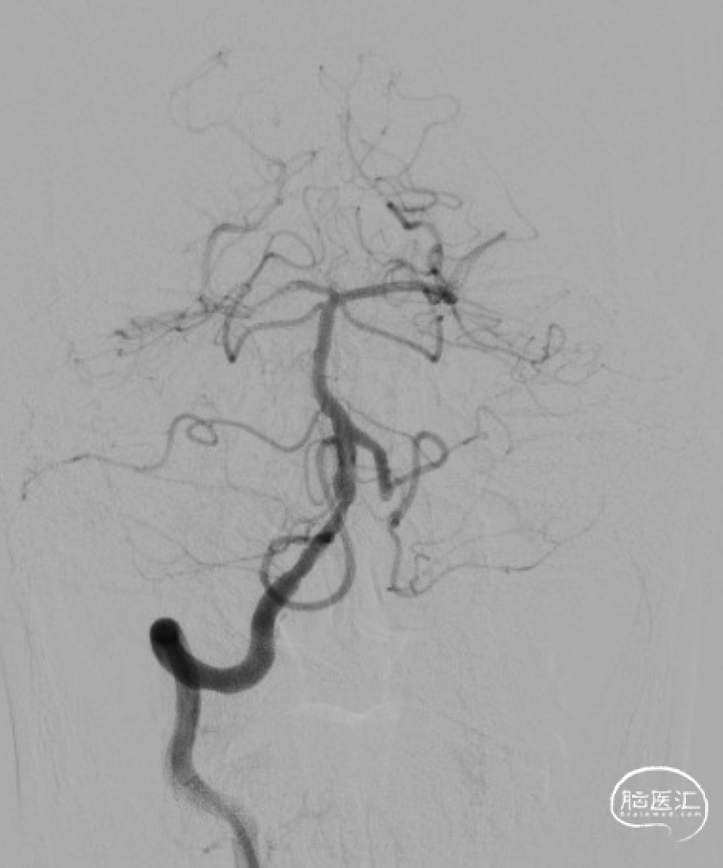

LSCA造影:LVA V2段闭塞。

RVA造影:RVA V4段重度狭窄。

DSA:RVA V4段重度狭窄90%。